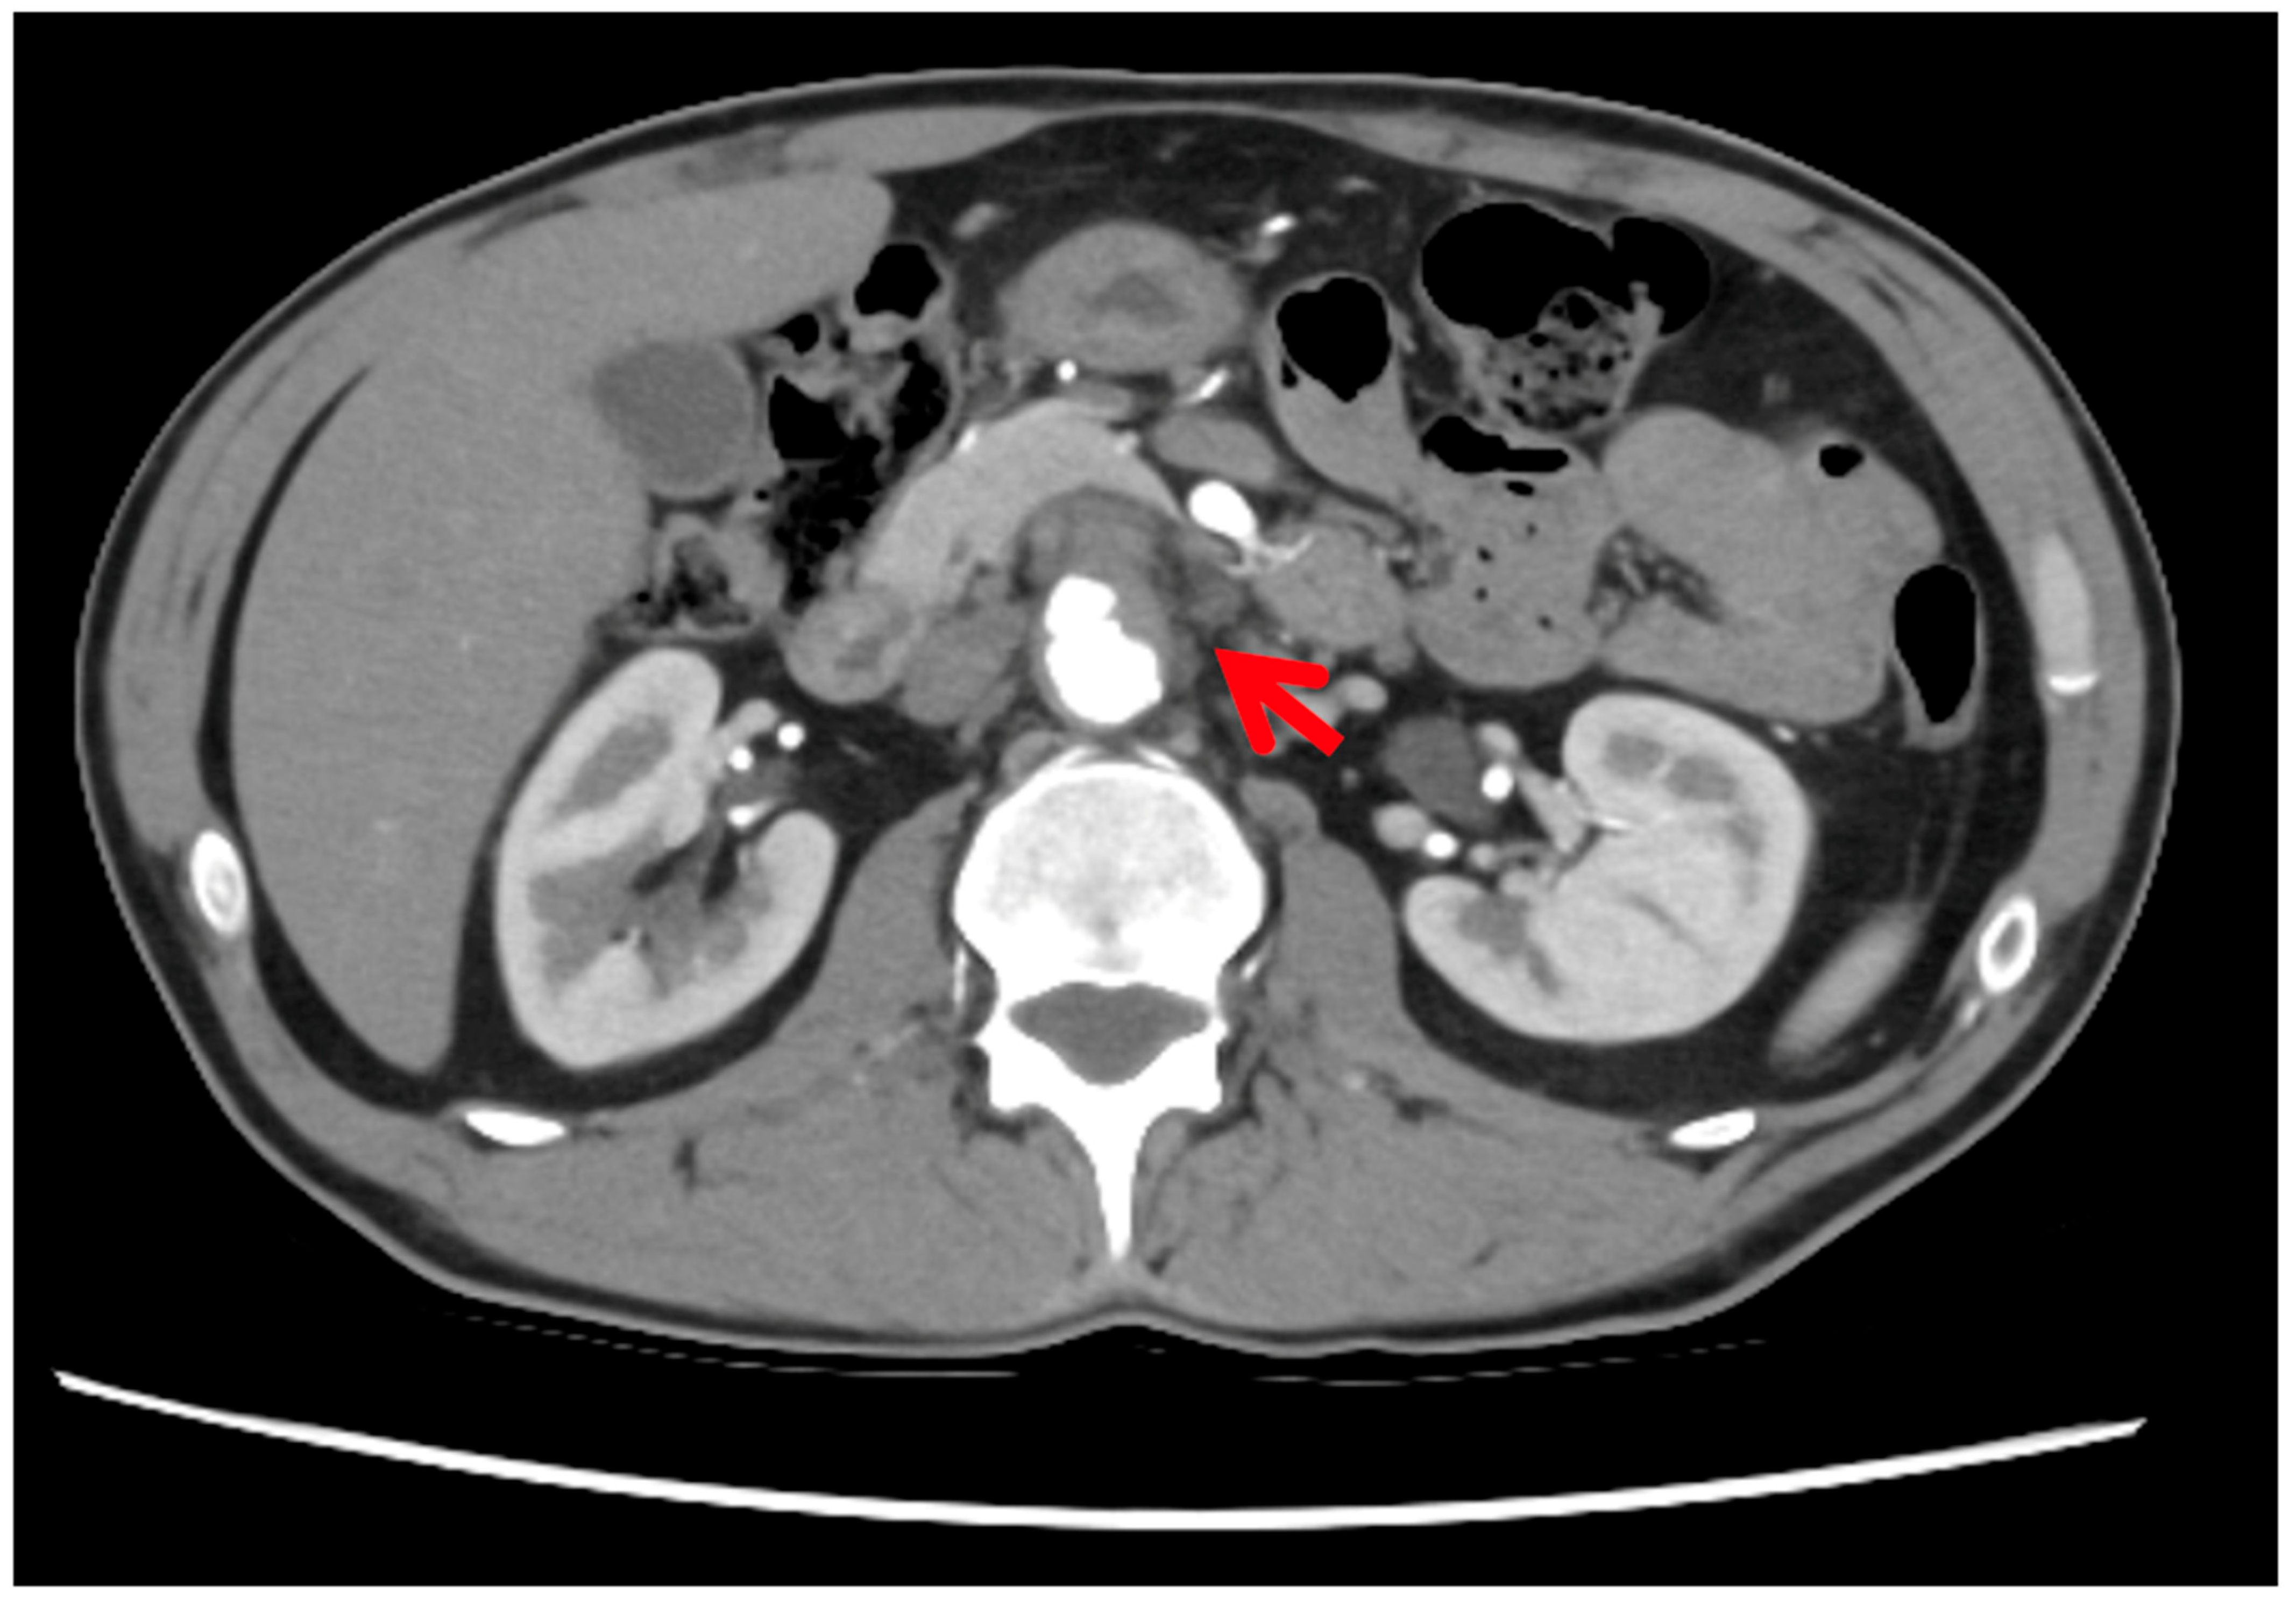

Computed tomography (CT) initially identified a non-specific lesion, which, upon review with fluorodeoxyglucose positron emission tomography (FDG-PET), was found to be a pre-aortic soft tissue mass with peripheral hypermetabolism and central hypometabolism, consistent with an inflammatory or infectious process (Figure 1). Arterial phase CT confirmed a 9 mm saccular false aneurysm from the anterior wall of the infrarenal aorta (Figure 2), with additional foci in the bilateral iliac arteries, consistent with mycotic aneurysms. Urine cultures later confirmed Mycobacterium bovis infection. The patient underwent successful endovascular stenting and anti-mycobacterial therapy, with excellent clinical improvement.

Figure 2.

Arterial phase axial computed tomography (CT) image showing a saccular false aneurysm from the anterior wall of the infrarenal aorta. A 12 mm non-thrombosed component is surrounded by a 24 × 22 mm thrombosed sac with peripheral enhancement and no calcification, consistent with a partially thrombosed mycotic aneurysm.